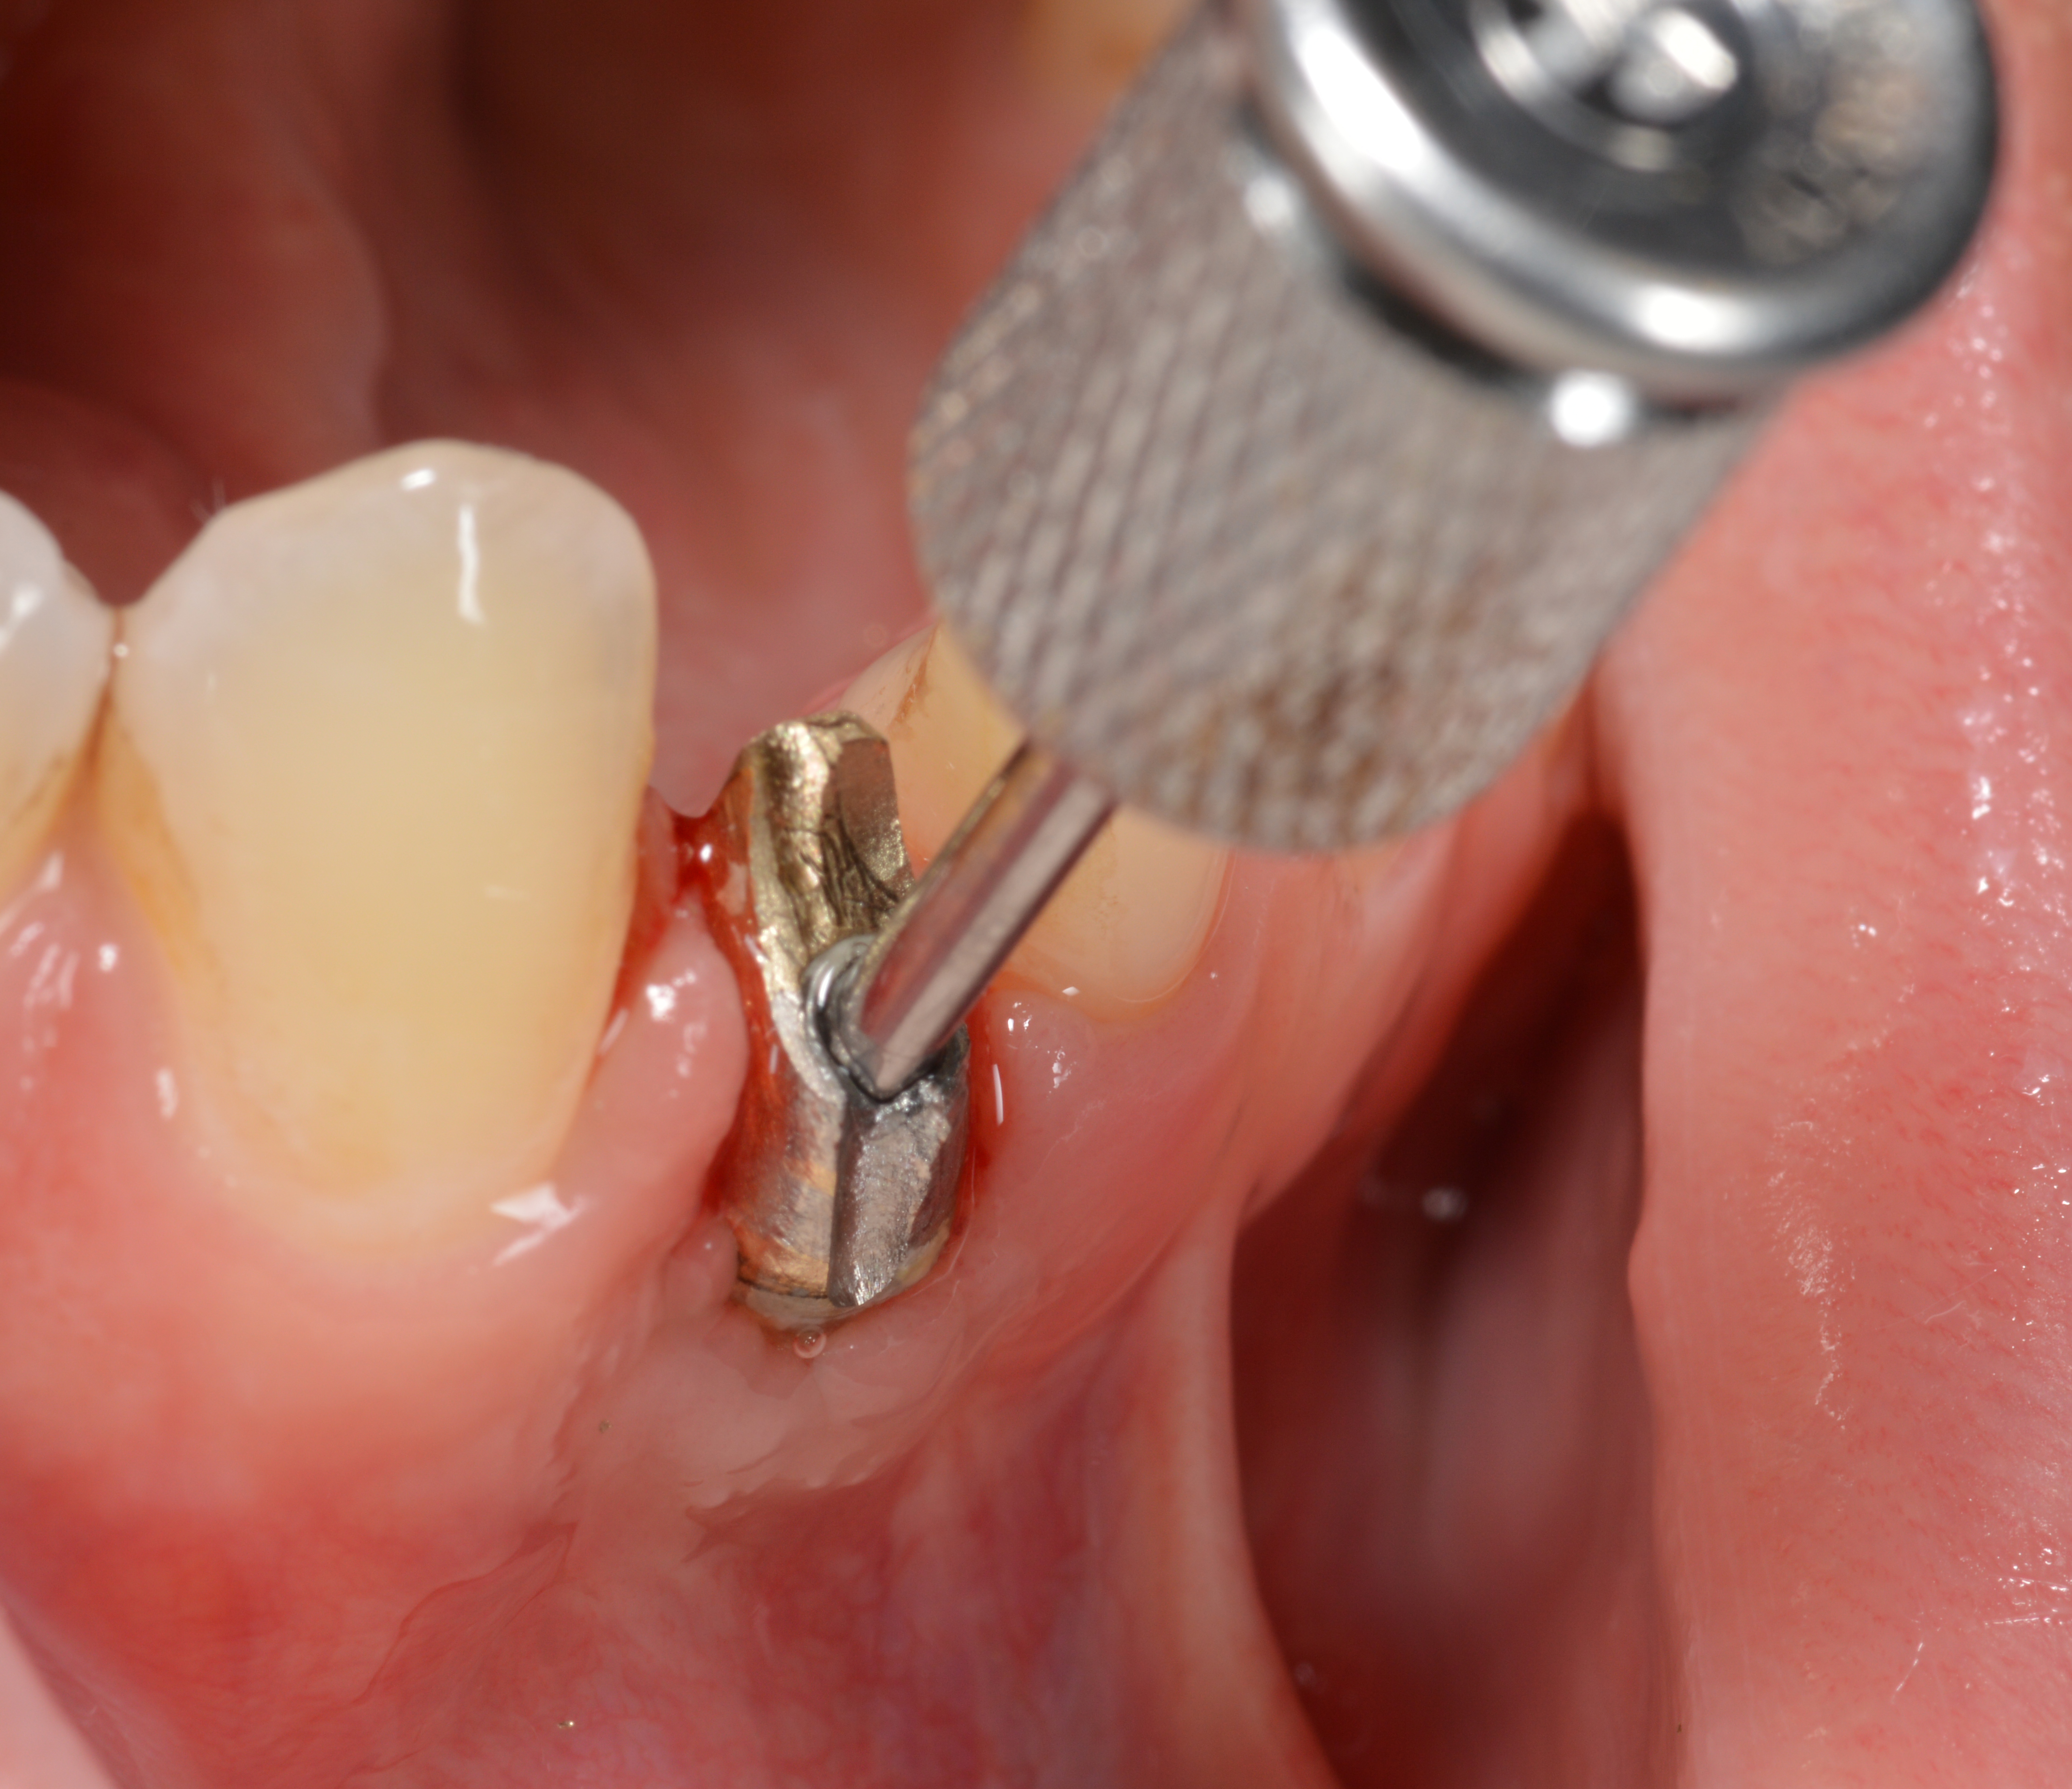

Fig 33. Excessive facial angulation of the implant placement shown with an abutment driver in the access screw hole.

Figure 33

Fig 38. A reverse-torque screw was placed into the implant.

Figure 38

Fig 39. A counter-torque device was placed over the reverse-torque screw.

Figure 39

Fig 40. The implant was easily unscrewed within minutes in a minimally invasive manner with less trauma to the surgical site.

Figure 40